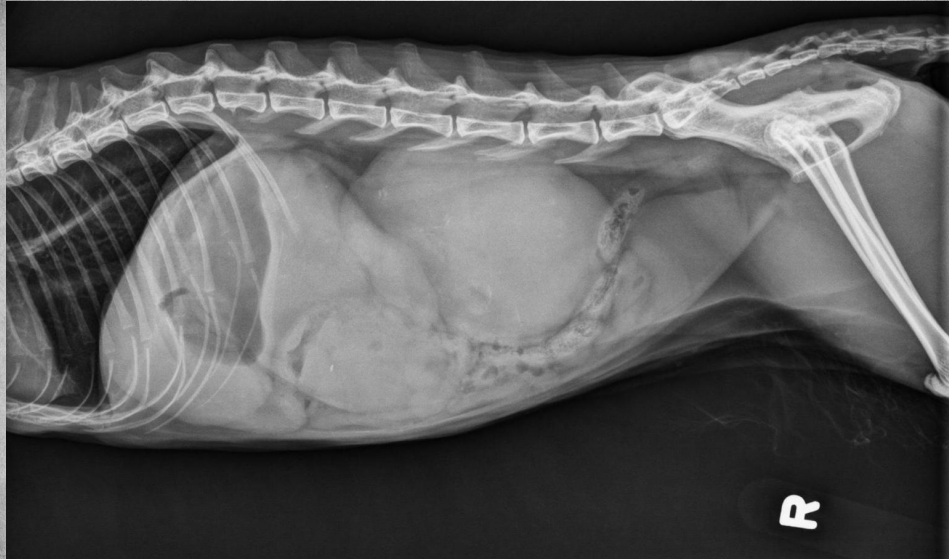

●9 yo mixed breed female dog

(sterilized)

●Increased ALP

● Impressive amount of subcutaneous and intra-abdominal fat.

● Enlarged liver – changed gastric axis pushed caudally, rounded edges, extending past the costal arch.

● At least two round soft tissue opacity structures superimposed on ventral liver (lateral view).

● Round soft tissue structure cranial to right kidney.

● Mass in adrenal gland or pancreas

● Hepatic nodules (benign vs metastatic disease)

SI gas is normal because bowels empty.